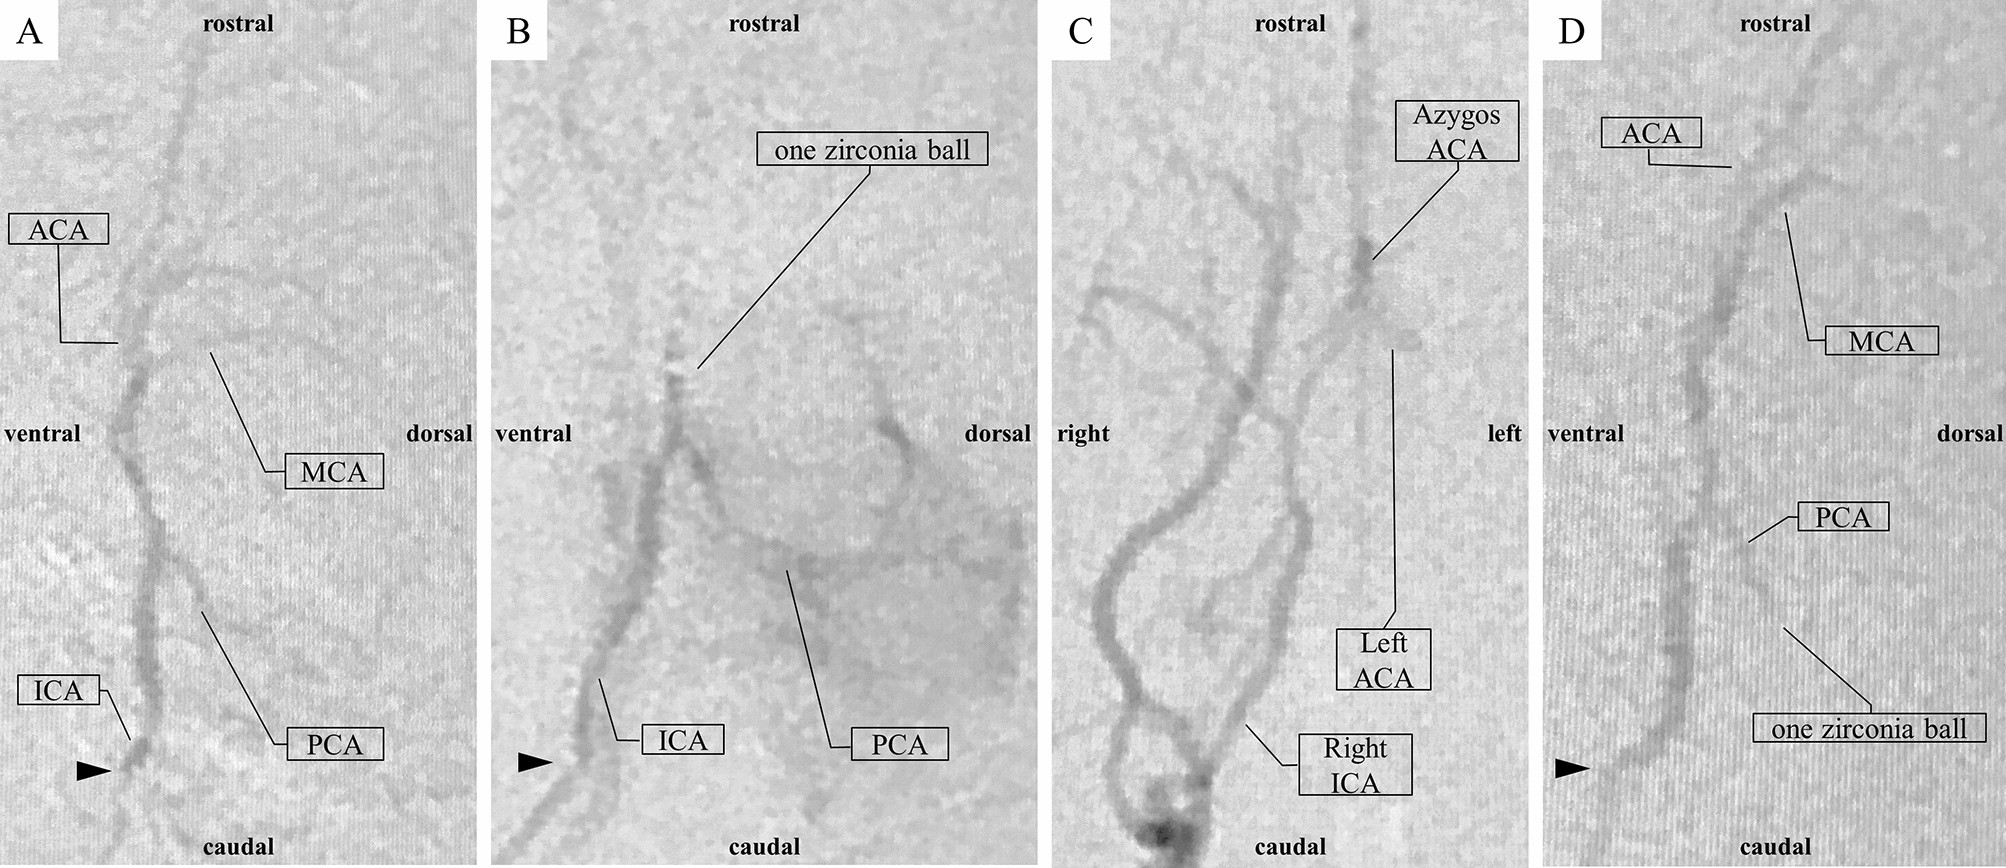

Figure 3

Angiography and embolization. The arrowhead shows the tip of the microcatheter. (A) Left ICA angiography (LAO angle = 80°). (B) The left ACA and MCA bifurcation was selectively embolized by one zirconia ball (LAO angle = 80°). The PCA was better visualized than before embolization. (C) Right CCA angiography (LAO angle = 0°). The left ACA retrograde flow is maintained through the right ACA. (D) The left PCA was accidentally failure embolized by one zirconia ball (LAO angle = 80°). ACA anterior cerebral artery, ICA internal carotid artery, LAO left anterior oblique, MCA middle cerebral artery, PCA posterior cerebral artery.